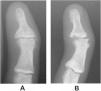

Protocol consisted in the study of both hands in all cases (pelota players and control group) through physical examination (Fig. 1A) and radiographic assessment of hand in anteroposterior and oblique positions (Fig. 1B). For radiographic assessment a longitudinal line from the axis of the mid phalanx was traced and the angle obtained between both lines was calculated using the reader of the angles from the software system incorporated into the radiographic visual display (Fig. 2). Data collection of case and control groups was performed in a standardised and homogeneous manner for both groups. Clinical and radiographic assessments were made by the corresponding author.

Acquired post-traumatic clinodactyly of both little fingers of the professional hand pelota player. (A) Image of the professional pelota player: bilateral clinodactyly and hyperkeratosis of the palm. (B) X-rays of the 5th finger of the hand in anteroposterior projection where post-traumatic clinodactyly may be observed.